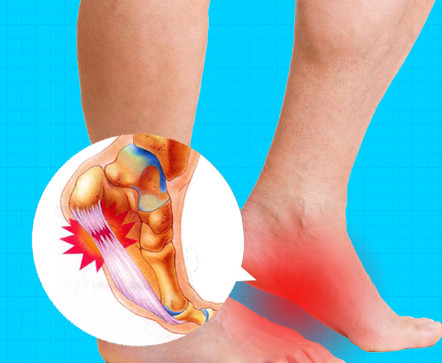

족저 근막염이란?

족저근막염이란 발바닥 뒤꿈치에 염증이 생기면서 나타나는 발바닥 통증을 일컫습니다. 이는 남성보다 여성이 2배 정도 많이 발병된다고 하는데, 그 원인은 과도한 발의 스트레스나 운동으로 인해 발병된다고 합니다. 이 밖에 몸무게의 급격한 증가나 평발도 발병 확률을 높이는 원인이 됩니다.

족저 근막염의 가장 흔한 증상으로는 아침에 통증이 매우 심하다는 점입니다. 그 이유는 밤사이에 족저근막이 수축되었다가 잠에서 깨서 일어나며 지면을 내딛는 순간 스트레칭 되면서 통증이 발생되기 때문입니다. 보통 원인은 종아리의 과단축으로 인하여 발바닥 근막이 당겨지면서 발병하는 경우가 대부분입니다. 때문에 족저 근막염을 예방하려면 평소 종아리와 발바닥을 같이 관리해 주어야 합니다. 만약 족저 근막염에 걸린 경우에는 생활 개선과 함께 필요에 따라 약물이나 의료적 치료가 병행되어야 합니다.